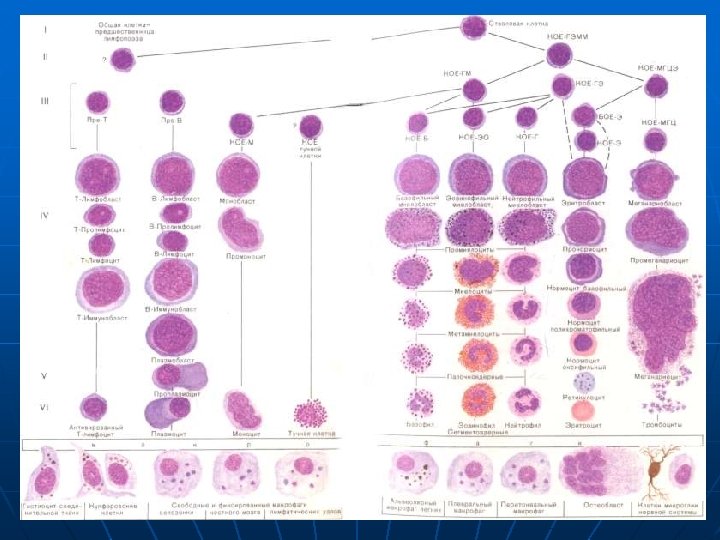

Лейкозы и агранулоцитозы n Острые лейкозы • Миелобластный • Лимфобластный • Недифференцируемый n • Промиелоцитарный Агранулоцитоз • Аутоиммунный (идиопатический) • Гаптеновый (анальгин, индометацин, бруфен, мерказолил и многие другие). Вирусы.

Лейкозы n n Клиника разная Диагноз по анализу крови и костного мозга Вариант лейкоза ставится по цитохимии Проблемы лейкозов • Геморрагический синдром • Анемический синдром • Вторичное инфицирование • Миелотоксическая панцитопения